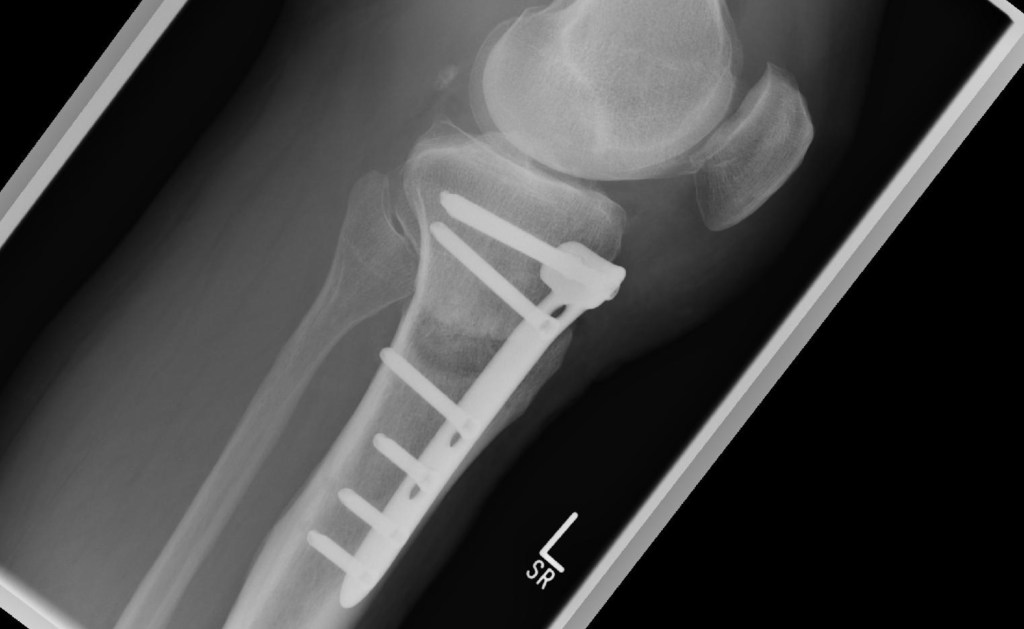

Die o. g. Frage haben sich bestimmt einige gestellt. Anhand der Zugriffszahlen in den letzten Wochen habe ich bemerkt, dass das Leben in meinem Blog scheinbar vermisst wird. Und es tut mir schon weh, dass ich momentan und auch in den nächsten Wochen nicht die Möglichkeit habe, sozusagen „fast live“ von den Barnimer Fußballplätzen zu berichten. Wer meinen Blog regelmäßig verfolgt, wird Anfang August diesen Eintrag (link) gelesen haben. Resultierend aus dieser Operation hat sich nun ein Folgeeingriff ergeben, der mich wiederholt in die Zwangspause gezwungen hat. Und diesmal noch deftiger als im August. Kurz erklärt, hat sich beim ersten Eingriff im Sommer ein Knorpelschaden vierten Grades im Innenbereich des Knies, gepaart mit einer Arthrose ergeben, welche eine Umstellungsosteotomie (HTO) des Knies durch eine Fehlstellung in der Beinachse erforderlich gemacht hat. Für Nichtmediziner einfach dargestellt: Ich hatte starke O-Beine und das Linke wurde nun begradigt. Hier sind drei Abbildungen, die einmal meine Beine im postoperativen Zustand zeigen und dazu zwei Fotos, auf denen zu sehen ist, was an meinem Unterschenkel gemacht wurde. Er ist „aufgekeilt“ worden und mit einer Metallplatte arretiert, so dass ich in Zukunft mehr mein Außenknie nutze, in dem noch einiges an Knorpelmaterial vorhanden ist. Klingt logisch, oder …?